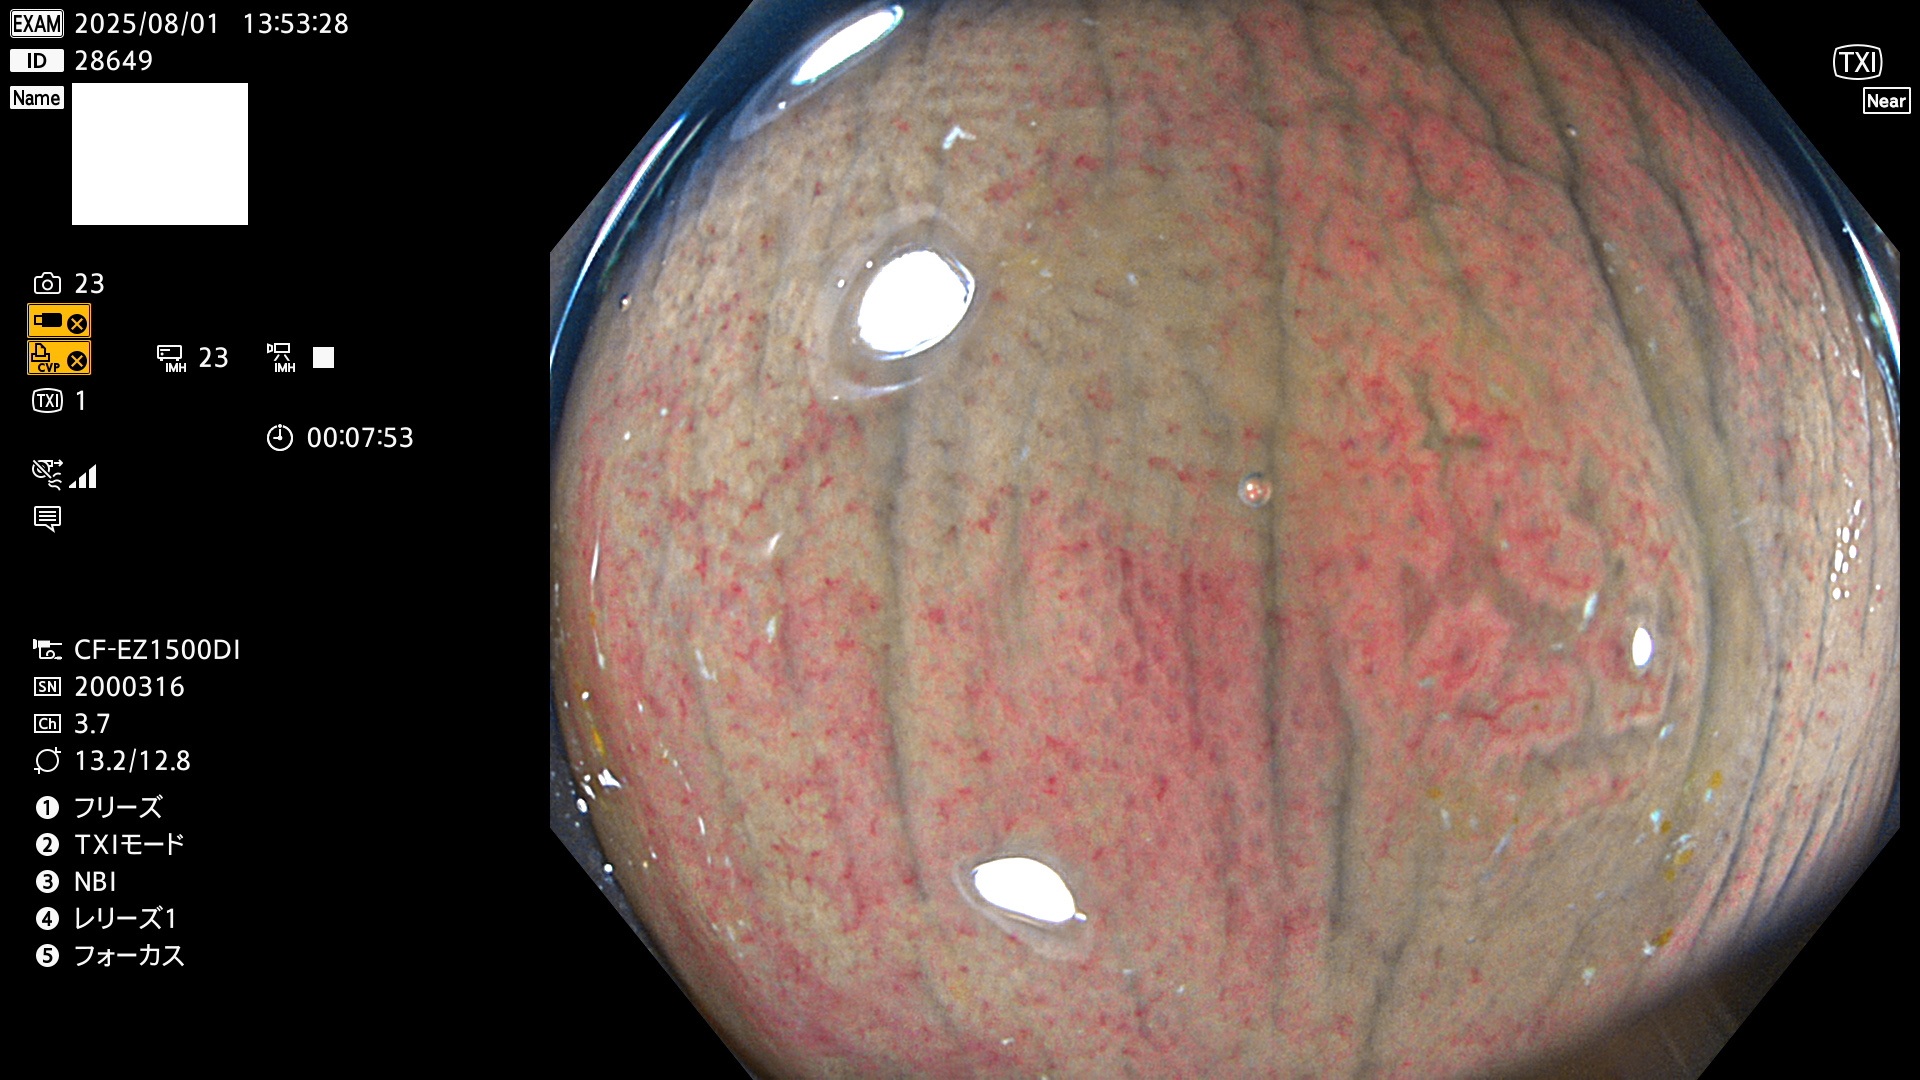

2025年7月31日〜8月3日の4日間(35件)5個 (Uc_ADR=5個/35人=14%)